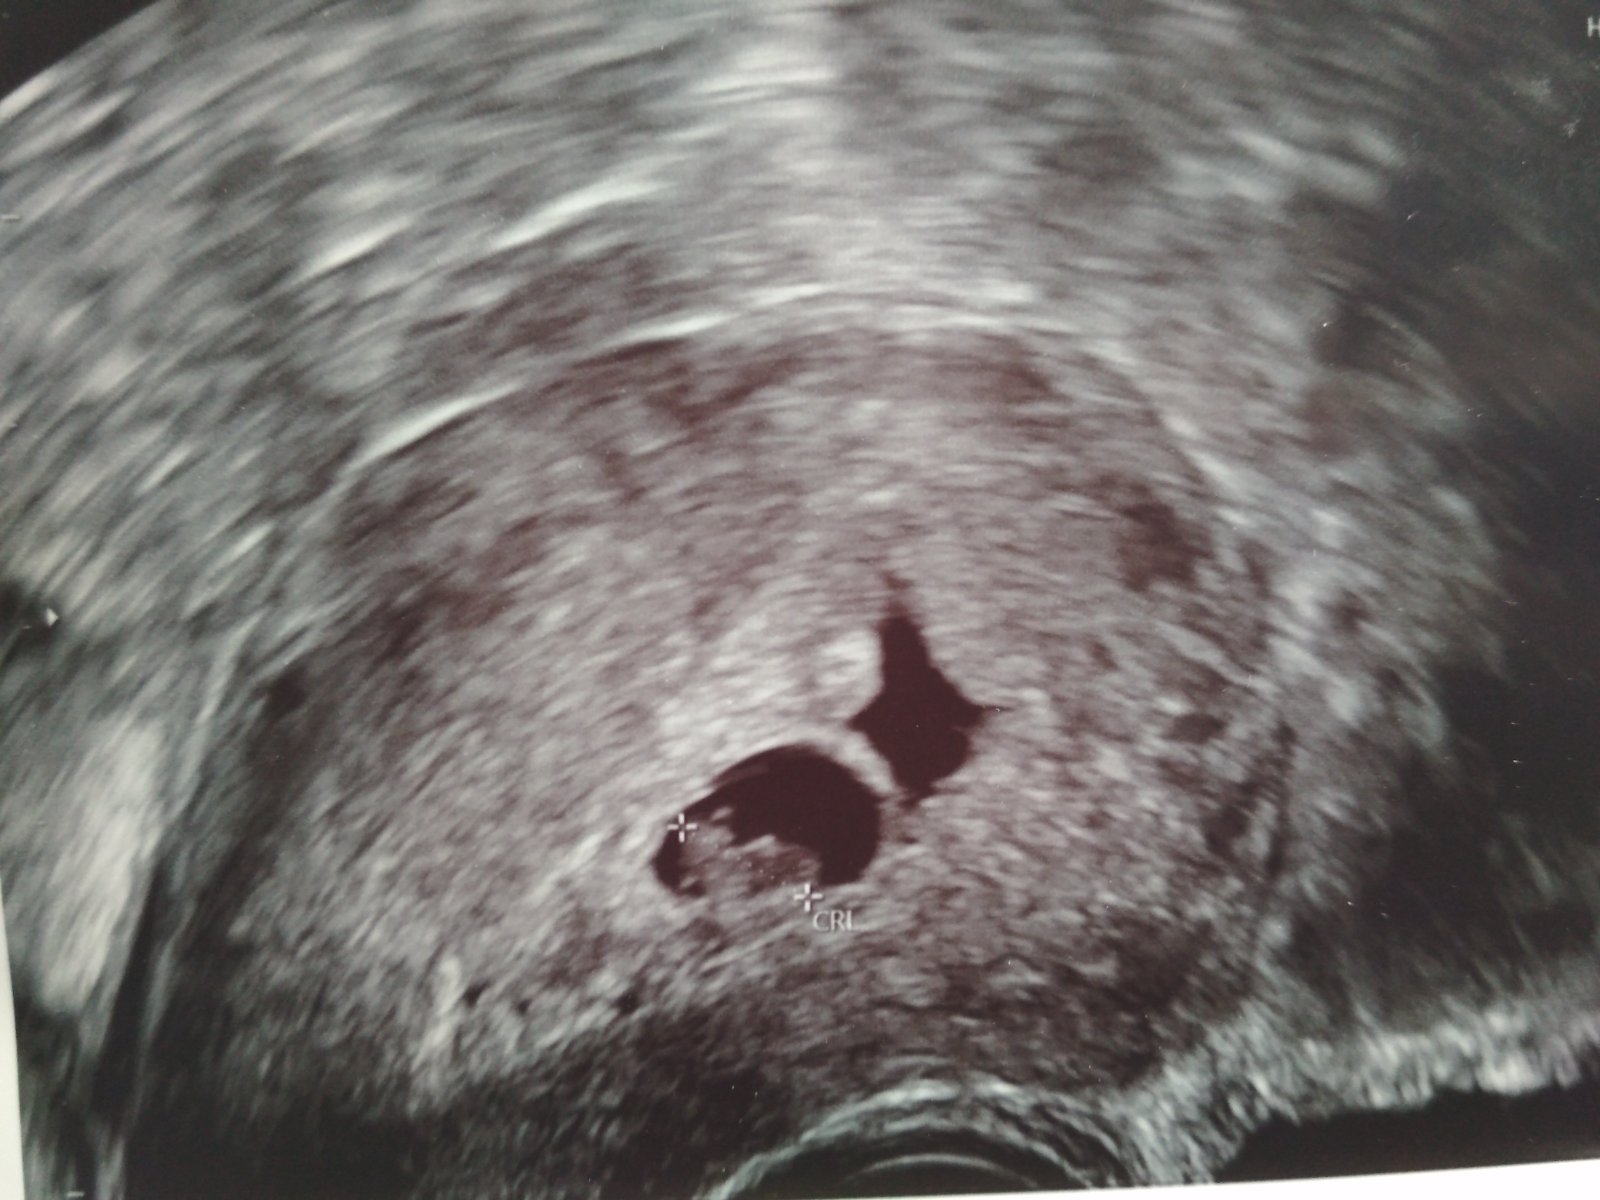

Dnes jsem byla na kontrole u dr, těhotenství dle ovulace 7+0, podle ult 6+5 ❤️ "Miminko" má skoro 8mm a srdíčko vije o stošest ❤️ Jenže je tam problém... Že nad plodovým vejcem je částečné odloučení a poměrně velké 😞 Dr říkala, že to odloučení pravděpodobně bude naplněné krví a je velká pravděpodobnost, že začnu špinit nebo krvácet... Dala mi léky na krvácení a jak se objeví nějaký náznak, mám to hned začít zobat a pokud to krvácení bude větší, tak hned na kontrolu ke své dr nebo do nemocnice, protože hrozí, že se to utrhne i s miminkem ... Utrogestan beru od //, kvůli předešlým problémům v těhotenstvích 😏 Strašně mě to vyděsilo, bojím se jít i na wc, abych tam nenašla krev 🙈 Máte někdo zkušenosti? Dopadlo to u vás dobře? 🙈😞 Mám mít klidový režim... Jenže s malými dětmi doma, to ne vždy jde, ale snažím se posedávat, polehávat 🤷 Přikládám fotku, kde je to odloučení vidět...